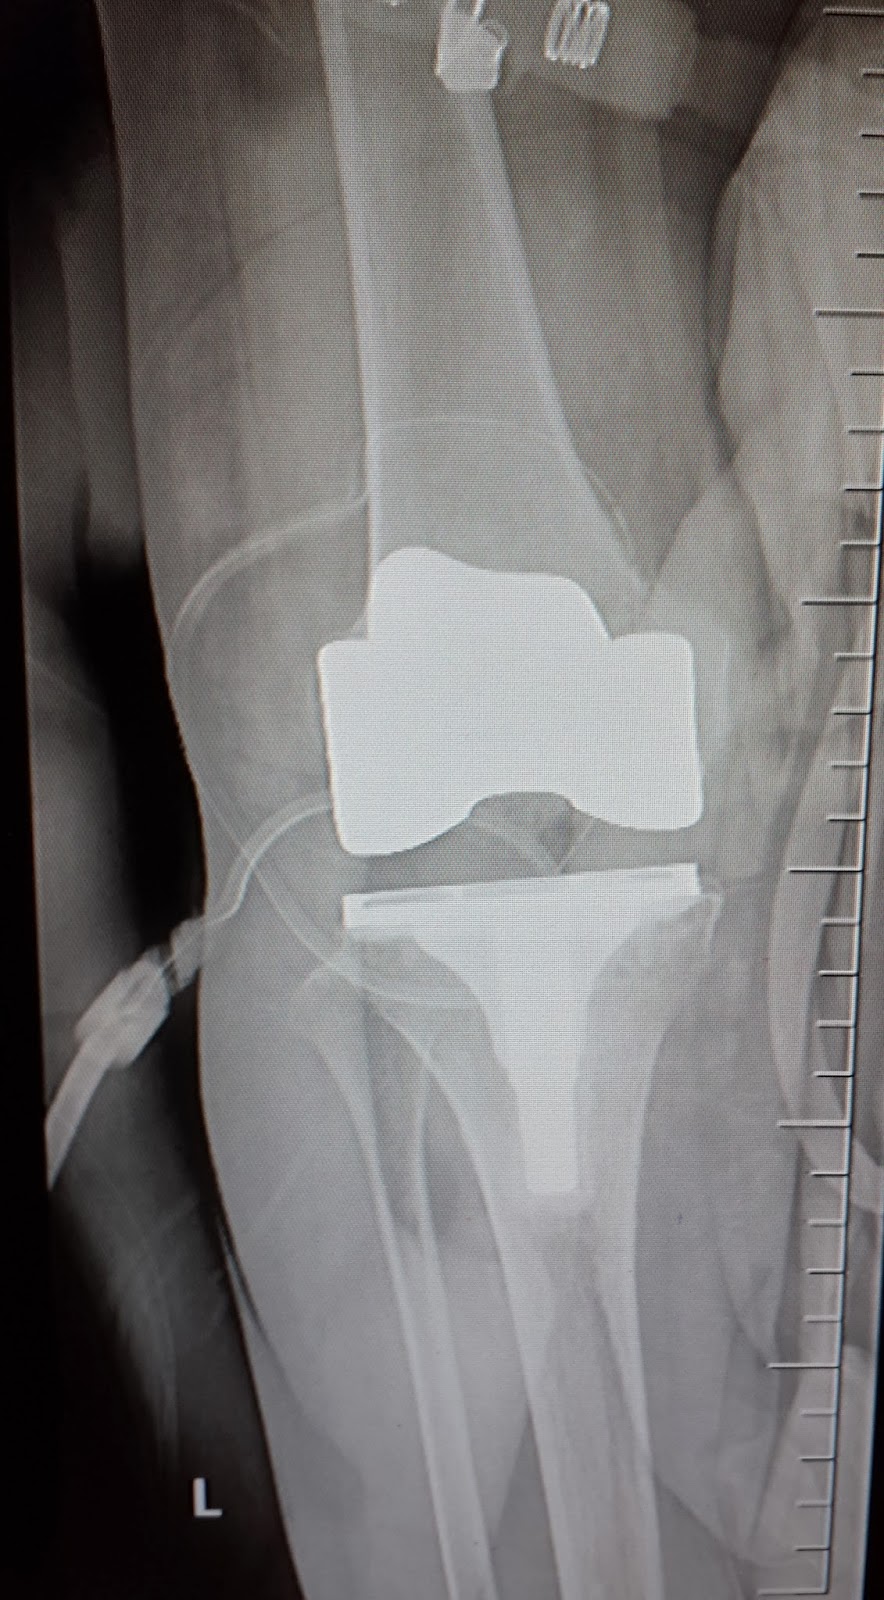

2. แก้ไขความผิดรูปของข้อเข่า ซึ่งส่วนใหญ่ผู้ป่วยมักจะมีอาการเข่าโก่ง การผ่าตัดเปลี่ยนข้อเข่าเทียมจะช่วยแก้ไขแนวของเข่าและขาข้างนั้นให้ตรง สามารถรับน้ำหนักได้ดี การเดิน และการทรงตัวของผู้ป่วยดีขึ้น ทำให้ช่วยเรื่องสมดุลของร่างกาย และป้องกันไม่ให้เกิดการหกล้มได้ง่ายซึ่งมีโอกาสทำให้เกิดกระดูกหักตามมา

ในปัจจุบันด้วยวิวัฒนาการทางการแพทย์ทั้งในเรื่องของการผ่าตัดรักษา ประสบการณ์ของแพทย์ที่ทำการผ่าตัด การพัฒนาเทคโนโลยีของข้อเข่าเทียมที่นำมาใส่แทนผิวข้อเข่าเดิมของผู้ป่วย รวมทั้งเทคนิคการดูแลควบคุมอาการปวดหลังการผ่าตัด ทำให้การรักษาด้วยการผ่าตัดเปลี่ยนข้อเข่าเทียมให้ผลลัพธ์ที่ดี ผู้ป่วยมีความพึงพอใจกับผลการรักษาด้วยการผ่าตัดเปลี่ยนข้อเข่าเทียมเป็นอย่างมาก และสามารถกลับไปใช้ชีวิตและท่องเที่ยวไปตามที่ต่างๆ ได้อย่างมีความสุข อย่ากลัวเลยกับการผ่าตัดเปลี่ยนข้อเข่าเทียม ท่านได้ประโยชน์จากการผ่าตัดเปลี่ยนข้อเข่าเทียมมากกว่าที่ท่านคิด ความกลัวเรื่องการผ่าตัดอาจจะทำให้ท่านพลาดโอกาสที่สำคัญอย่างหนึ่งที่จะทำให้คุณภาพชีวิตของท่านดีขึ้นมากกว่าสภาพก่อนผ่าตัด ในกรณีผู้ป่วยเข่าเสื่อมที่มีข้อบ่งชี้สำหรับการรักษาด้วยการผ่าตัดเปลี่ยนข้อเข่าเทียม